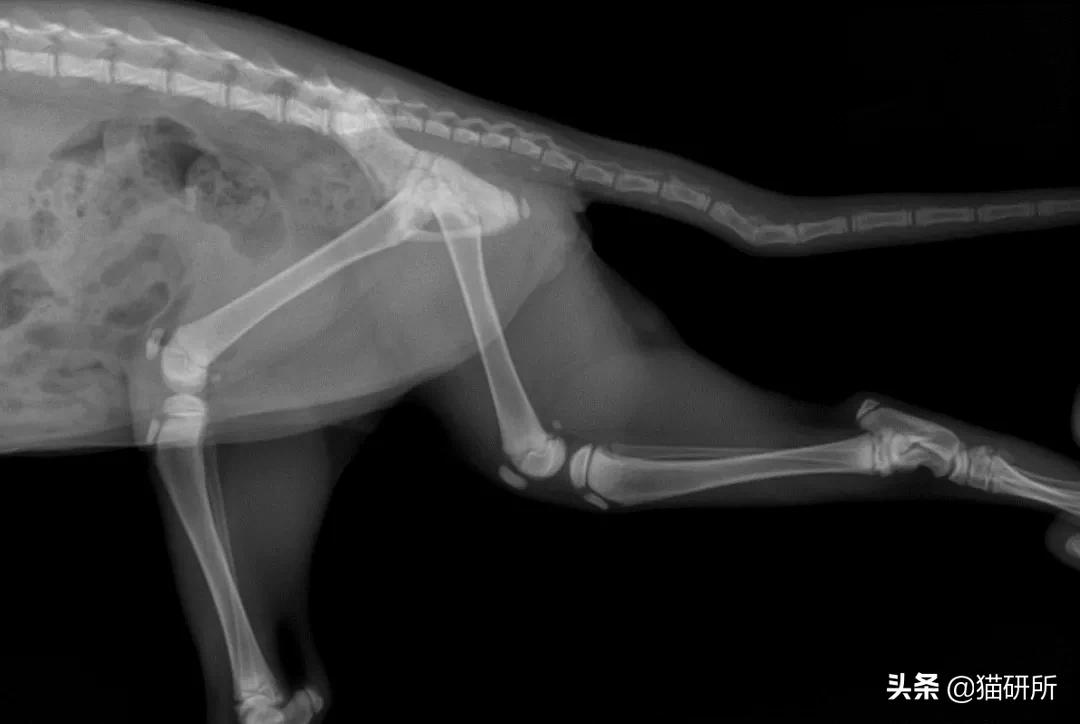

尾部骨折

尾部拉伤,在猫咪中比较常见。

轻微骨折很难发现,注意猫咪是否有排尿排便的异常,运动功能是否下降。通常,在没有这些异常情况下,尾部骨折不用手术处理。

尾骨骨折 图自:猫研所动物医院